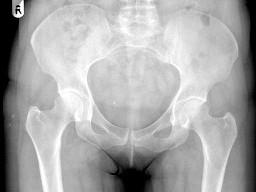

男,根据其正常盆腔影像图像,判断其最可能的年龄?(?)A.10岁左右B.30岁左右C.20岁左右D.80岁左右E.60岁左右

问题 男,根据其正常盆腔影像图像,判断其最可能的年龄?(?)

选项 A.10岁左右 B.30岁左右 C.20岁左右 D.80岁左右 E.60岁左右

答案 E